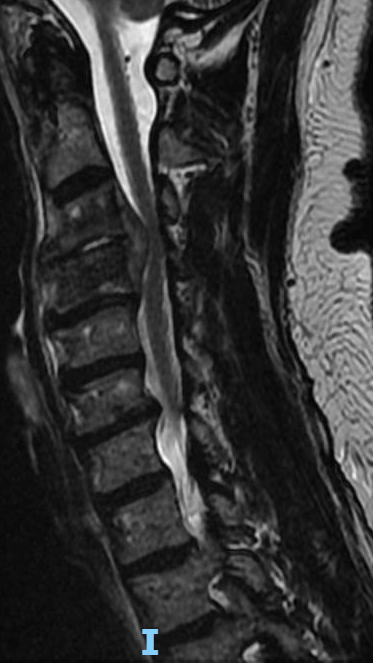

I performed a partial C4 corpectomy with fibular allograft -Abscesses can be more solid than expected -Partial corpectomy offers excellent decompression + stability -Material choice (titanium/allograft/autograft) matters less than thorough I&D and stabilization #cervicalspine

What would your surgical plan be for this patient with a cervical epidural abscess and severe arm weakness? #neurosurgery #physicaltherapy #chiropractor #spine #spinehealth #spinesurgery #cervicalspine